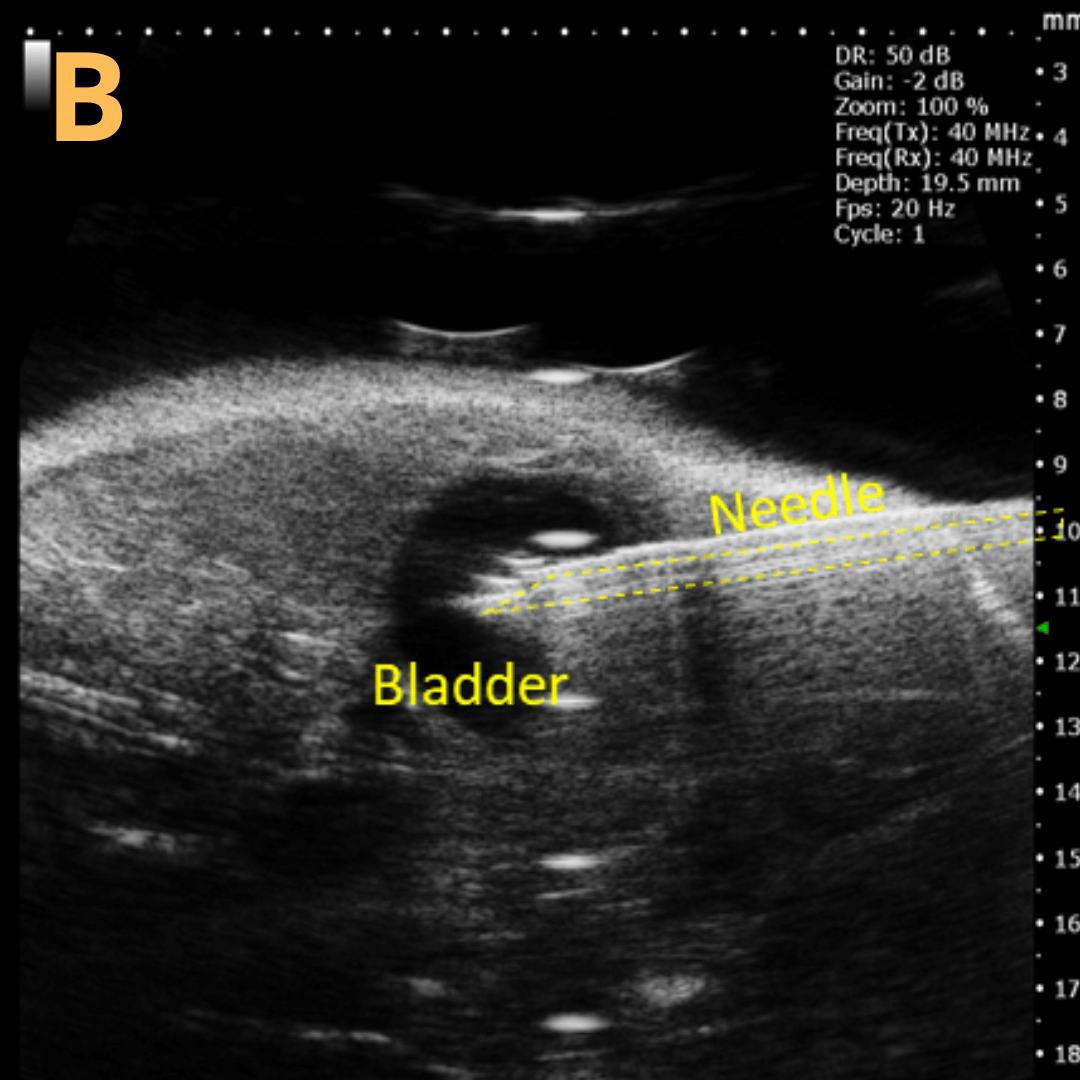

Ultrasound-Guided Injection

This is A) a B-mode video showing an injection into the bladder with B – D being still frames of B) before injection of any solution with the landmarks noted, C) during injection with bladder becoming notably larger, and D) the end of injection before needle will be removed. Imaging on a wildtype C57B6J mouse model – acquired images are from Stephen Zderic’s lab at the Children’s Hospital of Philadelphia.